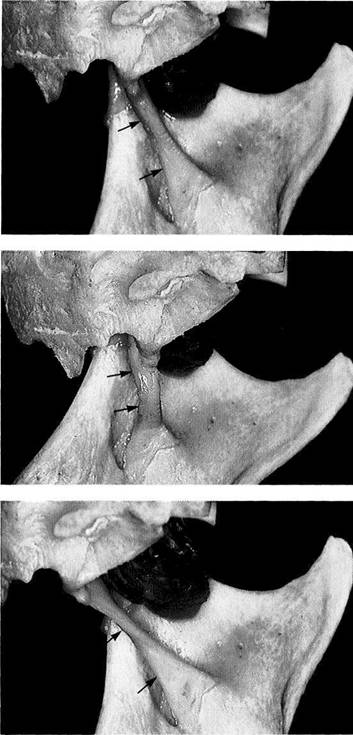

Sagittal relationships

Macroscopic anatomical preparation showing the relation of the fossa, disk, and condyle to one another in the sagittal plane. Because the shapes of fossae and condyles vary so greatly, it is not possible to determine a universally applicable measurement of the condylar position. Although the physiological (i.e. centric) condylar position is defined as the most anterosuperior position with no lateral displacement (arrows), this position depends upon the basic neuromuscular tonus.

Frontal relationships

Macroscopic anatomical preparation showing the relation of the fossa, disk, and condyle to one another in the frontal plane. In this plane, too, there is no standard geometric arrangement of condyle and fossa because of the variability of the hard and soft tissues (Yung et al. 1990). In this preparation the disk (arrows) is displaced laterally. Structures of the bilaminar zone (1) can be identified in the medial portion of the joint. The close proximity of the joint to the middle (2) and inner ear (3) can also be observed.

Horizontal relationships

A right temporomandibular joint viewed from above showing the relation of the fossa, disk, and condyle to one another in the horizontal plane. The lateral portion of the joint is near the left border of the picture. Near the upper border a section through the external auditory meatus can be seen (1). The roof of the fossa has been removed. Near the center of the picture lies the transition from the pars posterior (2) to the bilaminar zone (3). The central perforation was created during sectioning, and through it can be seen the upper surface of the condyle (arrow).